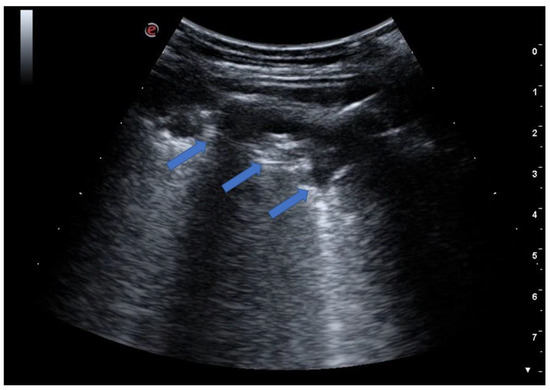

5. From the B-Lines to the Pathological Lung

5.1. Interstitial Syndrome